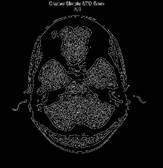

La mayoría de las investigaciones se dedican en la segunda etapa del procesamiento de imágenes donde se seleccionó los más utilizados y que mejores resultados ofrecen como la umbralización, el crecimiento de regiones y para terminar con esta etapa se implementaron cuatro algoritmos detectores de bordes el Canny, Prewitt, Sobel y Roberts. La primera etapa de procesamiento de imagen que se conoce como pre-procesamiento se implementaron los algoritmos de binarización, normalización, en escala de gris, filtro espacial, filtro pasa bajo, filtro mediana y Filtro Butterwort. Estos algoritmos son infalibles en la primera etapa y la última etapa se implementó los algoritmos de extracción de puntos y Transformada de Hough.

A continuación, se muestran las características y los resultados de los algoritmos utilizados en las Figura 4, Figura 5 y Figura 6 y se realiza una valoración sobre los aciertos de cada uno de ellos en el proceso de procesamiento de imágenes en las Tabla 1, Tabla 2 y Tabla 3, para la muestra se utilizó la herramienta de Matlab 2017 Figura 7:

En el procesamiento de imágenes se trabajó con varios algoritmos comportándose cada uno de ellos de diferentes maneras en correspondencia al tiempo de procesamiento y acierto en el trabajo que se necesitaba como se muestran en las siguientes imágenes A, B C, resaltado que los algoritmos Isodata, y Otsu su diferencia entre el acierto y el tiempo de ejecución son similares véase en la Figura 8, en el procesamiento basado en regiones sucede de igual manera con Cr y DFR.